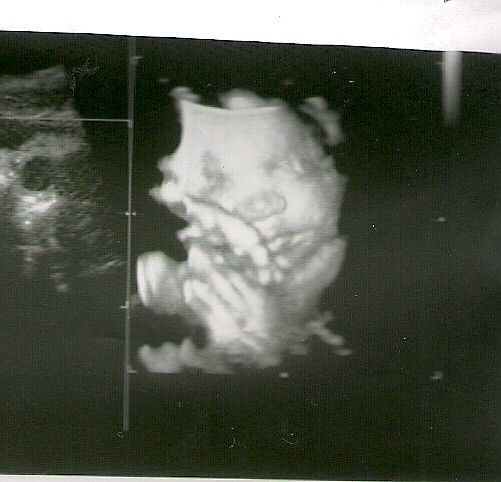

dostałam juz zaszczyk na konflikt... KTG w normie bez skurczy jeszcze... i za 2 tygodnie znow wizyta

dostane juz skierowanie do szpitala i znow badanie a w szpitalu zrobia mi ostatnie i czekamy na porod